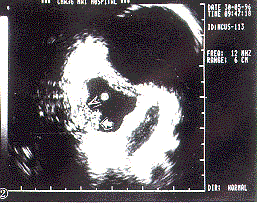

摘要 为探讨经内镜微超声探头(TEMP)对食管病变的诊断价值,对食管粘膜下肿瘤、食管癌、贲门失弛缓症、食管炎、食管息肉及静脉曲张等53例病变进行微探头超声检查。结果:TEMP检查能正确反映粘膜下肿瘤起源、癌肿侵犯深度,鉴别食管疾病的良恶性,判断硬化剂治疗食管静脉曲张的疗效;改变病人的体位,对检查不同部位病灶有助。结果说明TEMP检查对食管病变诊断与鉴别有较大的价值。